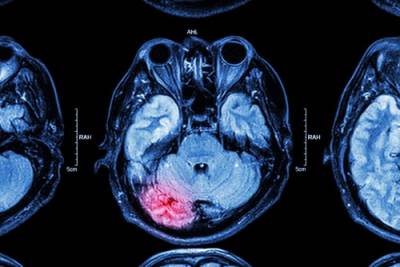

Seeking Compensation for a Traumatic Brain Injury Resulting in Cognitive or Psychological Harm

Trauma to the head sustained in a fall accident, car crash, or other traumatic events can damage the brain. Our brains control everything from physical movement to emotions and cognition. Consequently, traumatic brain injuries (TBI) can have a profound effect on the sufferers. The physical pain of a brain injury may eventually fade, but many TBI victims are left with cognitive impairment or psychological problems long after the visible injuries have healed. These problems can make it difficult if not impossible to work or carry out everyday tasks. If you or a loved one experienced a traumatic brain injury, it is important to explore your legal options.

Traumatic brain injury is one of the most dangerous types of injuries a person can suffer. TBIs not only cause physical problems like headaches and vertigo, but may also cause mental, cognitive, and psychological problems.